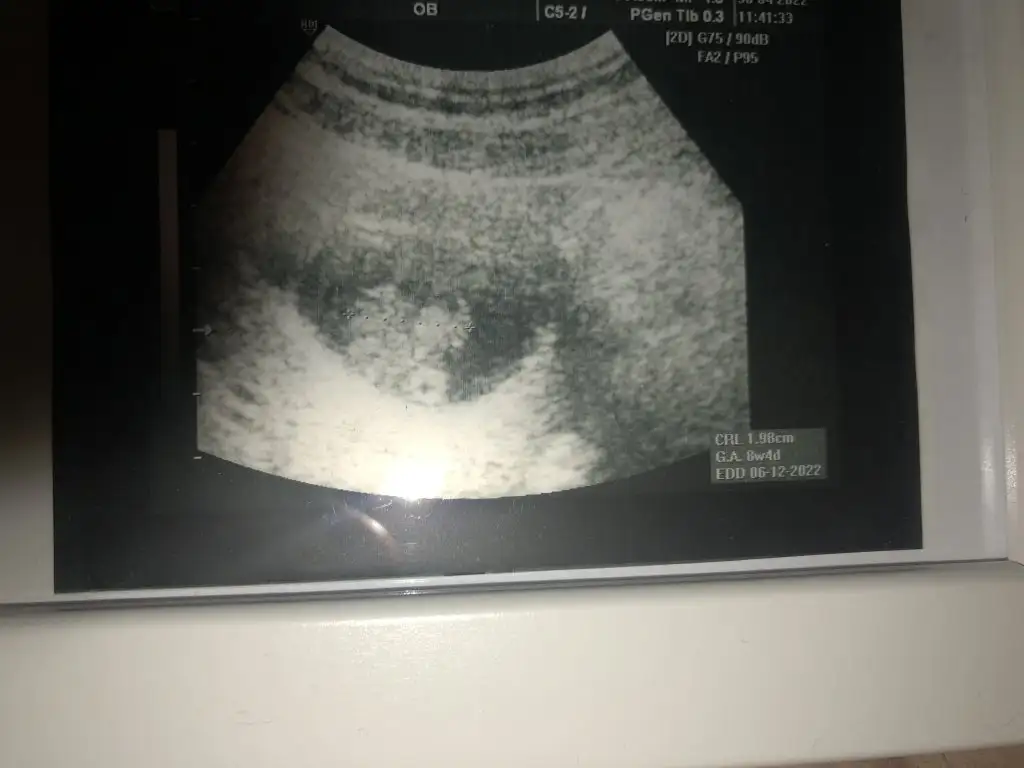

8+4 karından bakıldı tahmininiz var mı acaba 😇🥰

Eklentiler

• 364365A5-01EE-492B-BB24-2F22379988A1.webp

364365A5-01EE-492B-BB24-2F22379988A1.webp

17,9 KB · Görüntüleme: 69

• 8490FC3A-7EE1-4B23-80FD-52DCAE44B531.webp

8490FC3A-7EE1-4B23-80FD-52DCAE44B531.webp

19,1 KB · Görüntüleme: 67